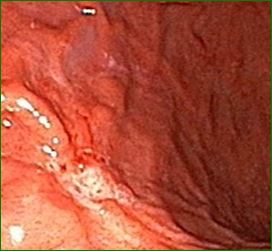

헬리코박터균에 감염되면 복통, 메스꺼움, 그리고 소화불량 같은 증상이 나타날 수 있어요. 특히 식사 후 상복부 통증이 심하다면 헬리코박터균 감염을 의심해 볼 필요가 있답니다.

치료 방법으로는 항생제 요법이 주로 사용되며, 위산 분비를 억제하는 약물도 함께 복용해요. 식이요법 역시 빼놓을 수 없죠! 자극적인 음식 대신 소화가 잘 되는 음식으로 위를 편안하게 만들어주는 것이 중요하답니다.

여러분, 이쯤에서 잠깐. 건강보험 잘 활용하고 계시죠? 헬리코박터균 치료는 간단한 내시경 검사만으로도 진단할 수 있는데, 여기서 보험 혜택을 챙긴다면 경제적으로도 부담을 줄일 수 있어요.